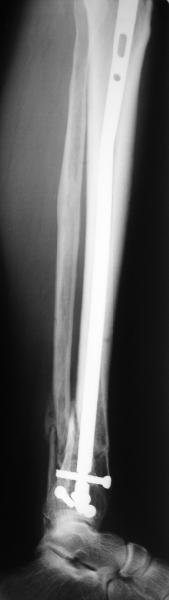

Сделали все-таки стержнем. На всякий случай просверлил дополнительное проксимальное отверстие, так что получилось три 45-градусных винта.

В дистракторе провеи спиц поболше в прокисмальном отделе, чтобы не разобщить фрагменты при сгибании колена. Комментарии и критика приветствуются.

We proceeded with nailing using a small wire distractor, with few wires at the proximal end to prevent displacement with forced knee flexion. Images attached. Comments and critics are welcome.

It is often a problem nailing upper tibial fractures. There is a tendency to apex anterior angulation as well as valgus alignment. Your entry point on the AP view seems to have been kept the same. How did you manage to maintain alignment? Any intra-operative pictures of your technique?

The lateral view shows your entry point to be quite posterior and I think this is recommended to avoid anterior angulation. Were you concerned about intra-articular penetration?

Overall an excellent post-op x-ray. Well done.